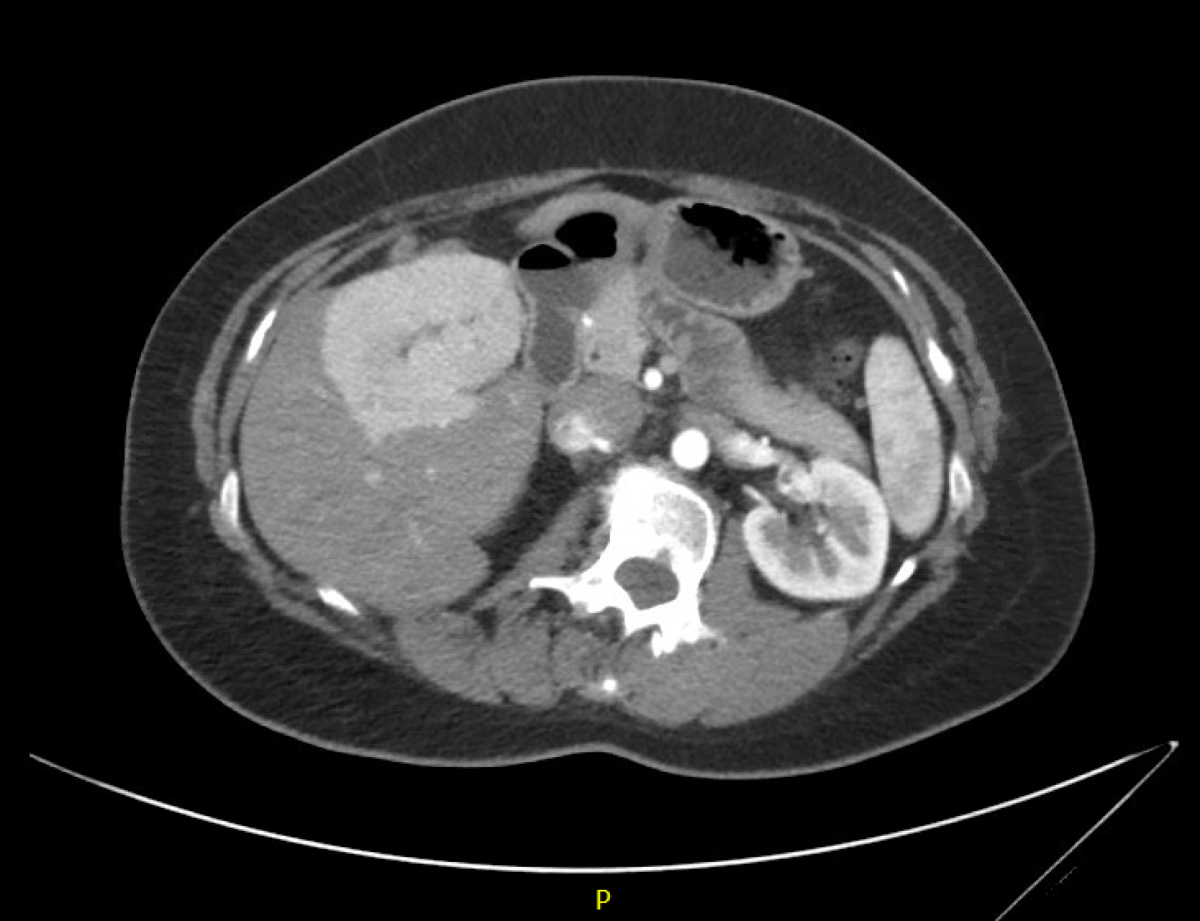

You see a 65-year-old man with a history of hepatitis C-related cirrhosis and a new diagnosis of hepatocellular cancer. He was recently found to have hepatitis C by his primary care doctor who he saw for right upper quadrant pain. He was referred to you after an ultrasound showed a vague **10-cm heterogeneous mass in the right lobe of the liver with absence of blood flow in the right portal vein.** He is genotype 1a, bilirubin is 0.6, AST 67, ALT 60, INR 1.2, platelet count 100,000, and AFP 12,000 ng/mL. His MRI is shown in the figure. It demonstrates a **large tumor in the right lobe of the liver with tumor invasion/thrombus of the portal vein.** A chest CT shows no pulmonary metastases. He should be referred for which of the following treatment options? A. Radiofrequency ablation B. Liver transplant C. Hepatitis C treatment D. Resection **E. Sorafenib**

Radiofrequency ablation would be an option for tumors generally 3 cm or smaller. ## Footnote -- This patient presents with hepatocellular carcinoma (HCC). The imaging findings are characteristic, and therefore a biopsy is unnecessary. Given that the imaging confirms the diagnosis of HCC, continued observation without further therapy would be incorrect. This would be graded as Barcelona stage 0 (very early stage) given its size of \<2 cm and unifocal nature. Sorafenib is indicated in stage C disease (multifocal with metastasis or with tumor thrombus in the portal vein), and would not be used in this case. Given the absence of portal hypertension (Child-Pugh class A), the small size of the lesion, and the patient’s lack of comorbidities, this patient would be a candidate for resection of the lesion and should be referred to an experienced hepatobiliary surgeon. If signs of portal hypertension were present (Child-Pugh B/C), the patient would then be a transplant candidate and should be referred appropriately. TACE may be used in patients with stage A disease (those with tumors \<3 cm in size or multifocal tumors \<3 cm in size). In stage 0 lesions, indirect comparisons favor survival and recurrence outcomes in patients who undergo resection compared to TACE, and as such, the American Association for the Study of Liver Diseases recommends resection as first line, if the patient is an appropriate surgical candidate.